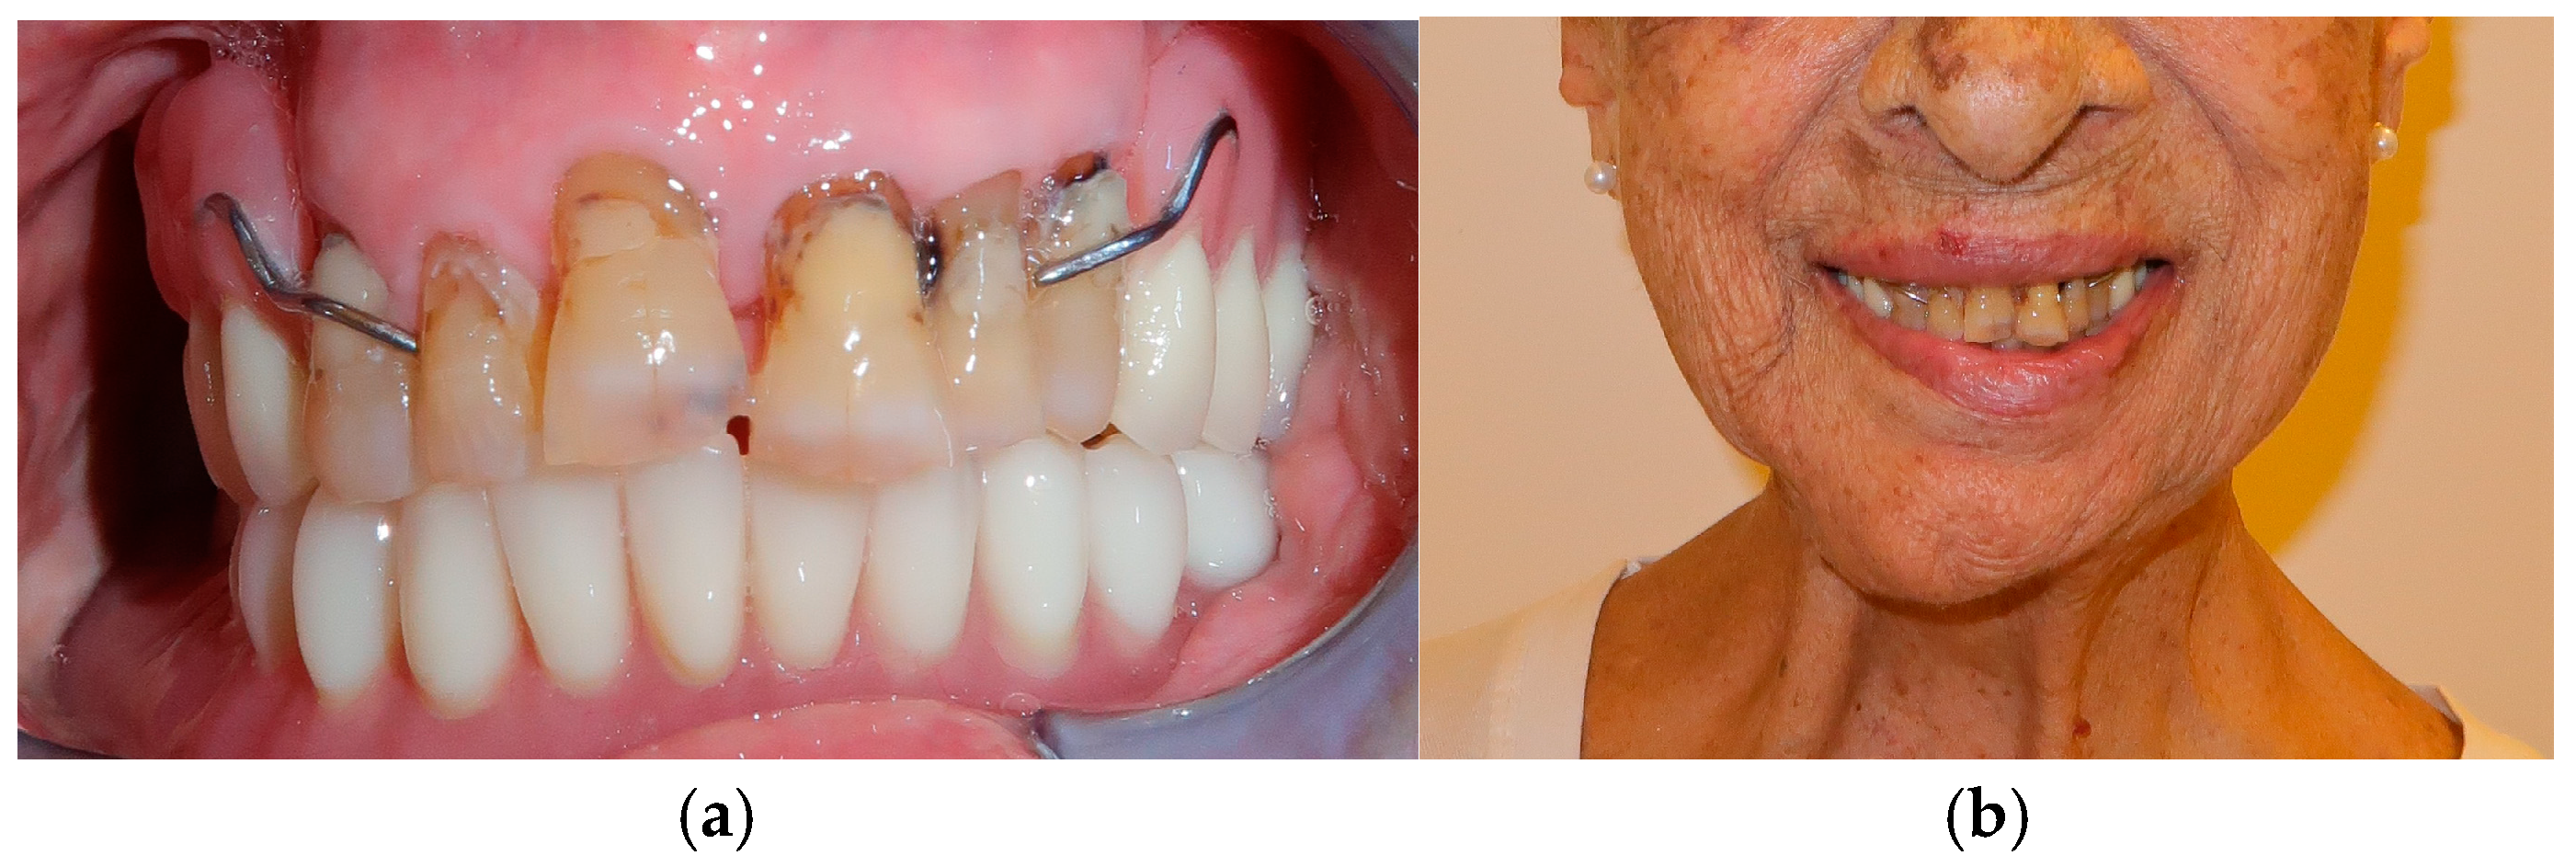

The patient in Case 1 had undergone surgery to remove a tumor that intersected the angle of the mandible. (L2) (Figure 1 and Figure 2). The upper elements were extracted soon after due to periodontal and endodontic issues. After being initially rehabilitated with a complete removable prosthesis (to regain function and aesthetic), two implants were subsequently placed in the 3.2 and 4.4 areas, and the final prosthesis was built in resin with a ball retention mechanism (Figure 3 and Figure 4).

Figure 1. Patient with hemimandibulectomy L2 in lateral (a) and front (b) extraoral view.